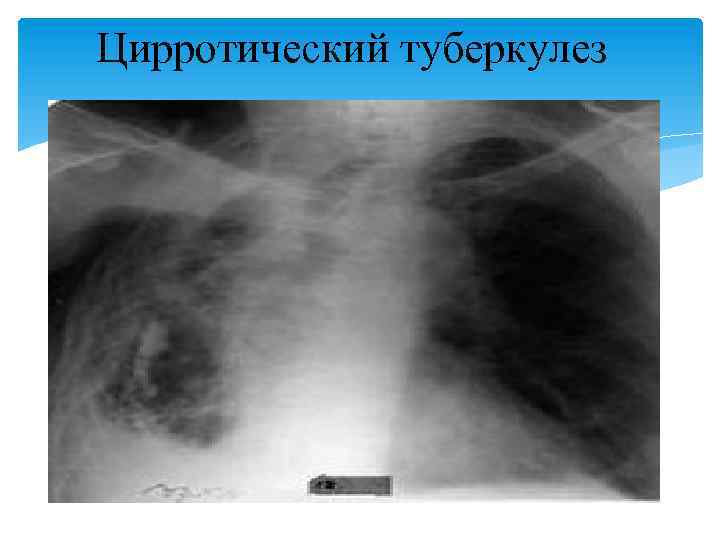

Цирротический туберкулез

По мере затихания обострения симптомы интоксикации постепенно уменьшаются вплоть до полного исчезновения, исчезает или уменьшается кашель и выделение мокроты. При физикальном исследовании в области пораженной доли отмечается притупление жесткое, иногда бронхиальное, дыхание. Часто выслушиваются постоянные влажные мелкопузырчатые хрипы. Изредка бывает кровохарканье. В мокроте непостоянно выявляются МБТ, особенно при наличии полостных изменений. Рентгенологаческая диагностика. Рентгенологическая картина цирротического туберкулеза характеризуется большим полиморфизмом. Цирротические изменения в легких обычно четко отграничиваются от легочной ткани, наблюдается выраженное затенение патологического процесса с уплотнением плевры и смещением органов средостения в сторону цирроза. В легочной ткани имеются изменения туберкулезного характера в виде полиморфных очагов, рубцовых изменений, наличие одиночной или множественных туберкулем.

В непораженных участках и в контрлатеральном легком имеются признаки эмфиземы. Полостные изменения — бронхоэктазы, буллы, крупнокистозные и щелевидные образования, возможно являющиеся остаточными кавернами. Диагностика цирротического туберкулеза осуществляется по данным анамнеза и комплексного клинико-диагностического обследования. Дифференциальную диагностику проводят с цирротическими процессами другой этиологии. Лечение. Госпитализацию в стационар противотуберкулезного учреждения больных цирротическим туберкулезом легких проводят в период обострения. Лечебный и двигательный режим определяется состоянием больного; питание соответствует диете № 11. Химиотерапия носит строго индивидуальный характер и проводится в соответствии с данными о лекарственной устойчивости МБТ.